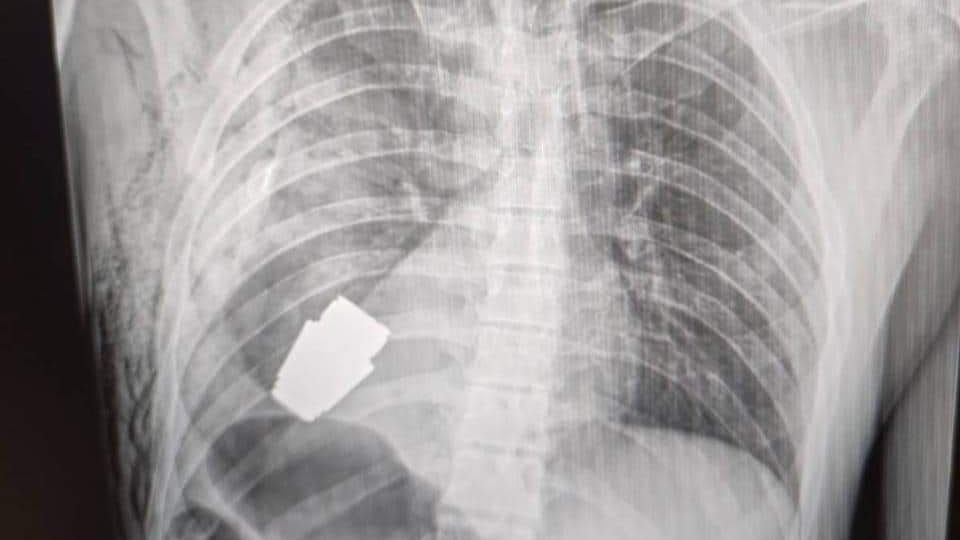

Das sogenannte VOG-Geschoss steckte im Brustkorb des Mannes.